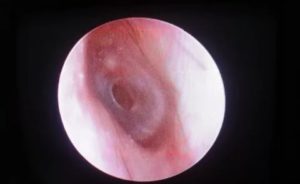

Барабанная перепонка — это тончайшая и непроницаемая для жидкости и воздуха мембрана. Она отделяет наружное ухо от среднего. На нее возложены 2 важные функции в организме человека: передача звуковых колебаний и защита полости от проникновения инородных веществ.

Структура барабанной перепонки очень нежная. Поэтому она легко повреждается в результате механических воздействий или патологических состояний. Это приводит к возникновению перфорации — образованию разрыва и отверстия.

При появлении симптомов, указывающих на перфорацию барабанной перепонки, необходимо обратиться к врачу-травматологу или отоларингологу. После осмотра пораженной области проводится отоскопия. В случае обнаружения дефектов мембраны переходят к более детальной диагностике патологии. Она состоит из следующих мероприятий:

Барабанная перепонка представляет собой тонкую эластичную пленку в полости уха, выполняющую важную функцию восприятия и передачи звуковых волн. При малейшем повреждении, называемом перфорацией, механизм проведения звука нарушается. В результате снижается слух, возрастает риск воспаления ушной полости.

Перфорация барабанной мембраны носит механический, термический, химический или физиологический характер. При незначительном повреждении восстанавливается самостоятельно, в остальных случаях назначается операция.